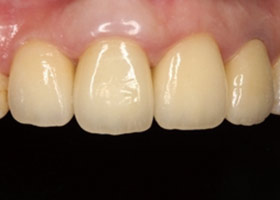

假牙完成後,植牙與自然牙,

真假難辨;病患恢復自信的笑容。